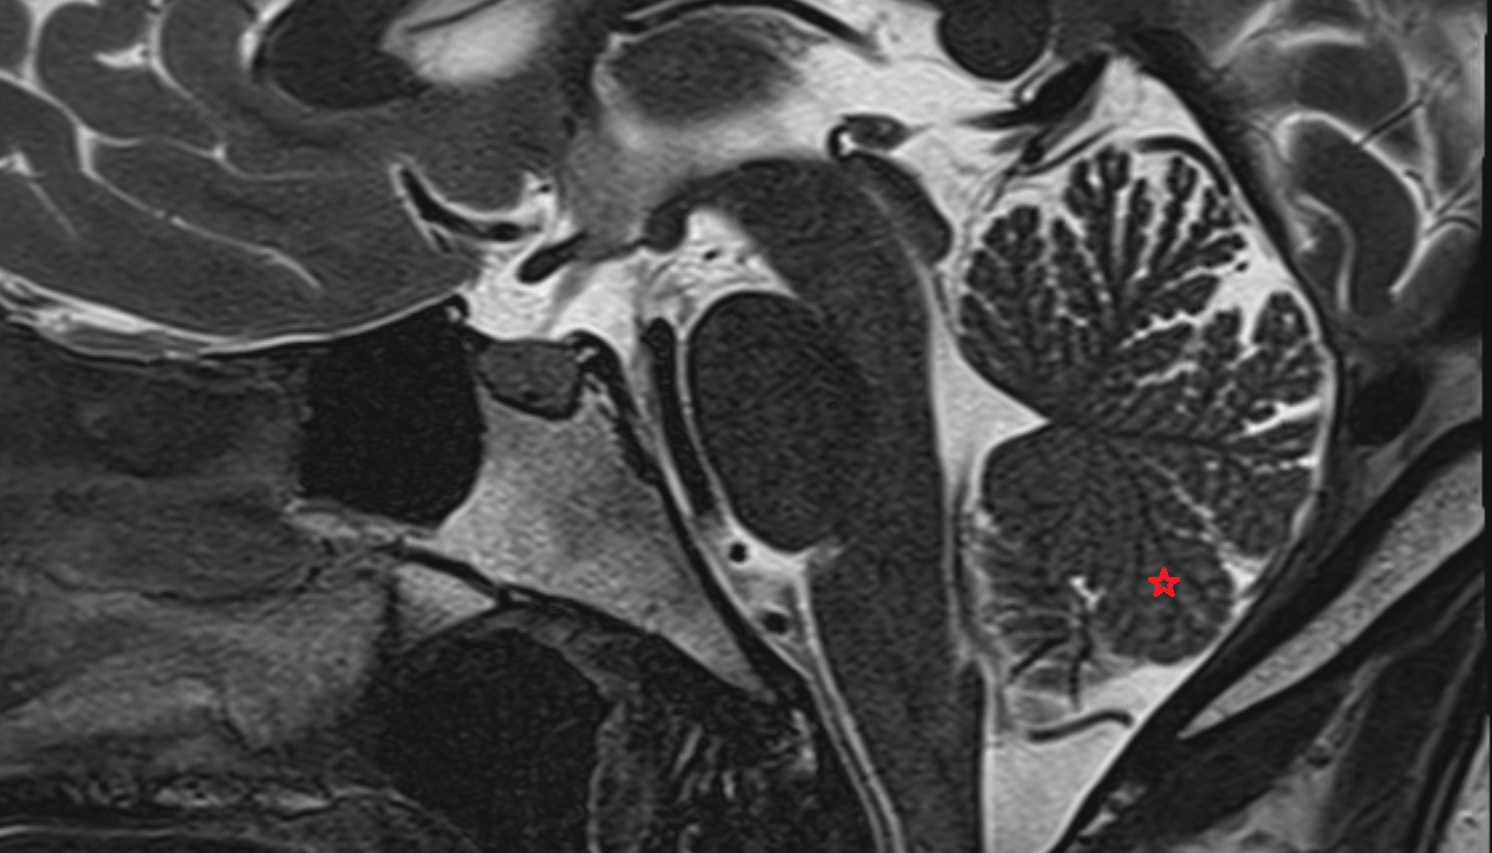

- Cerebellar tonsil (H IX)

- Tonsil of cerebellum